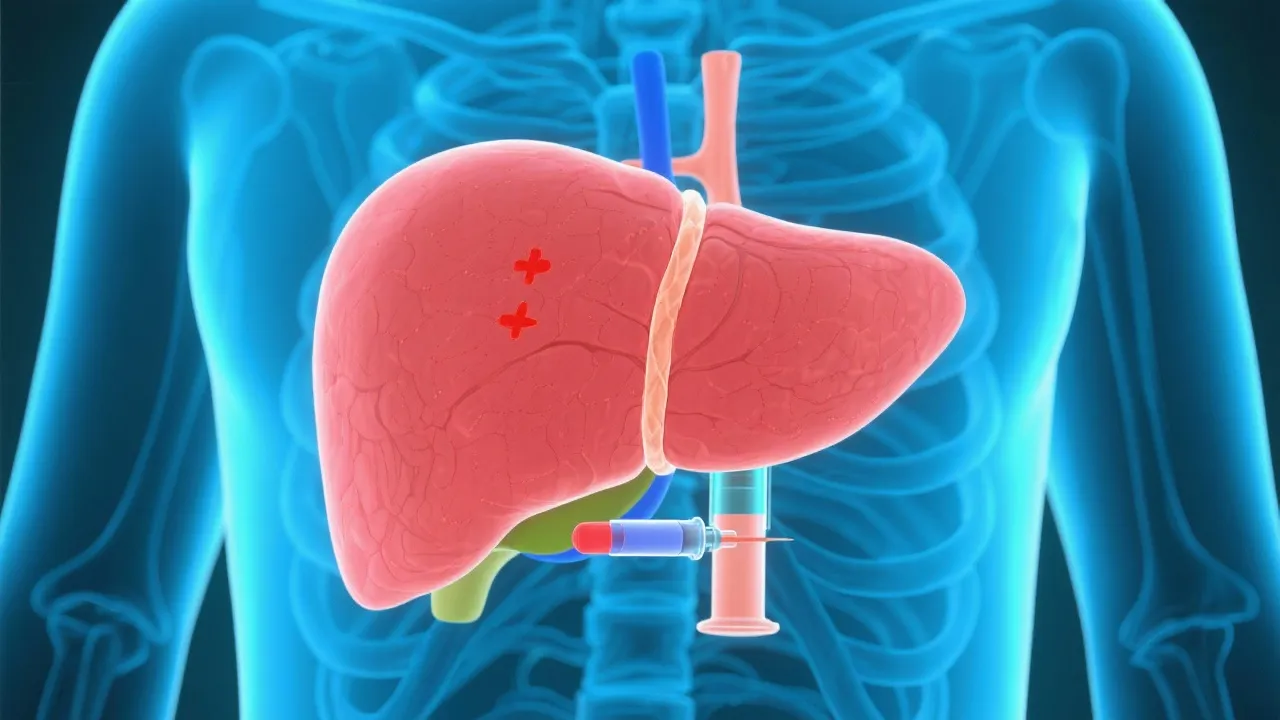

Non-alcoholic fatty liver disease (NAFLD) is an increasing health concern worldwide, leading to further complications such as hepatocellular carcinoma (HCC). This article delves into the connection between NAFLD and related HCC, discussing underlying mechanisms, risk factors, and potential preventive measures. It aims to provide an in-depth understanding of the disease progression and the latest research findings to enlighten healthcare professionals and the general public.

Non-alcoholic fatty liver disease (NAFLD) has emerged as a prevalent chronic liver condition globally. It is characterized by excessive fat accumulation in liver cells not caused by alcohol consumption. With lifestyle changes and the rising global obesity epidemic, NAFLD's prevalence has surged, affecting millions of individuals across various demographics. Recent studies have shown that NAFLD can progress into more severe liver conditions, including non-alcoholic steatohepatitis (NASH) and hepatocellular carcinoma (HCC). Recognizing the implications of this progressive liver disease is essential, as it not only impacts individual health but also places a significant burden on healthcare systems worldwide. Understanding the link between NAFLD and related HCC is critical for developing strategies to curb its growing epidemic.

NAFLD is increasingly recognized as a leading cause of HCC without cirrhosis. This form of cancer arises due to prolonged inflammation, fat accumulation, and liver cell damage. Medical experts emphasize that the liver's inflammatory response to fat deposition can trigger a cascade of events leading to fibrosis, necrosis, and ultimately the emergence of HCC. Notably, the progression from NAFLD to HCC often occurs in the context of metabolic syndromes like obesity, type 2 diabetes, and dyslipidemia.

The transition from NAFLD to HCC involves complex biological mechanisms, including chronic inflammation, oxidative stress, and genetic mutations. Chronic inflammation in the liver typically accompanies fat accumulation and is triggered by the release of pro-inflammatory cytokines. These cytokines can recruit immune cells to the liver, exacerbating inflammation and setting the stage for fibrosis and cancerous changes. Hepatic stellate cell activation plays a pivotal role in liver fibrosis, advancing the risk of HCC. As these cells become activated, they transform into myofibroblast-like cells, contributing to collagen deposition and scarring in the liver.